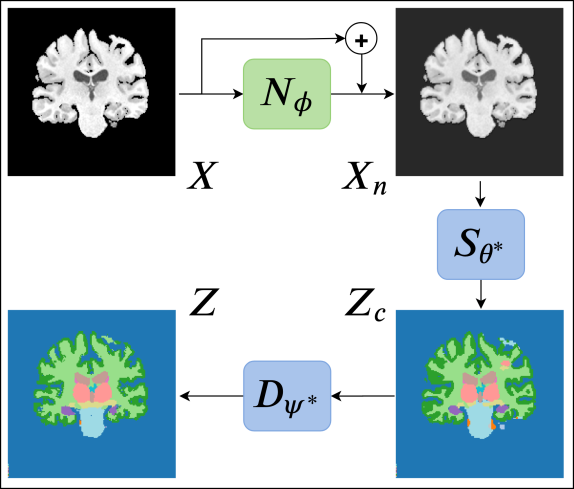

We hypothesize that in the absence of knowledge about the TD during the initial training, it may be necessary to introduce some adaptability into a segmentation CNN in order to enable it to deal with images arising from new scanners and / or protocols. With this in mind, we propose a segmentation CNN design that concatenates two sub-networks: a relatively shallow image normalization CNN, which we refer to as the image-to-normalized-image (I2NI) CNN, followed by a deep CNN that segments the normalized image, which we refer to as the normalized-image-to-segmentation (NI2S) CNN. During the training phase, we train both sub-networks jointly, in a supervised fashion, using a SD training dataset. At inference time, we freeze the parameters of NI2S, but adapt those of the I2NI for each test image. During inference, SD samples are not required. This test-time adaptation is driven by requiring that the predicted segmentation be plausible (according to the segmentations observed in the SD dataset), and for dictating such plausibility, we employ denoising autoencoders [15] (DAEs). The test-time adaptation in the proposed method is a part of the inference procedure and does not require any sample other than the test sample at hand. DG through such a test-time adaptation strategy allows adapting a network to any test image independently during inference, which is not possible in UDA and other DG methods.

The workflow of our test-time adaptation method is depicted in Fig. 1. We leverage the available ground truth segmentations in the SD training dataset, , to train a DAE, , that maps corrupted segmentations , which are not necessarily similar to those in the SD training dataset, to “denoised” segmentations , similar to those in the SD training dataset. The details of this training are explained in Sec. 3.3. For the time being, let us assume that we have a trained DAE, . For a given test image and a set of parameters for the I2NI CNN, , we treat the segmentation predicted by as a “noisy” or “corrupted” segmentation. We pass this noisy segmentation through and obtain its denoised version. Now, we update the parameters of the adaptable I2NI CNN, , so as to pull the predicted segmentation closer to its denoised version:

| (2) |

where is a similar loss to that in Equation 1. Eqn. 2 denotes the test-time adaptation that we carry out for each test image . This optimization is done iteratively (using either gradient descent or a variant thereof). At the beginning of the optimization for a test image, segCNN trained on the SD likely predicts a corrupted segmentation if the test image is not from SD, such as the one shown on the bottom-right in Fig. 1. The DAE takes this prediction as input and proposes a corrected segmentation, such as the one shown on the bottom-left in Fig. 1. Now, the parameters of the adaptable I2NI CNN, , are updated so as to minimize the dissimilarity between the DAE input and output. As the optimization proceeds, the segmentation predicted by segCNN becomes increasingly plausible, that is, similar to those in SD training dataset. Therefore, the DAE input and output become similar, resulting in small loss values and convergence of the test-time adaptation. Importantly, the adaptable normalization module is relatively shallow and has a relatively small receptive field. Thus, the adaptation cannot introduce large structure alterations but it is free to change the contrast of the input image. The optimization runs for a pre-specified number of iterations and the optimal I2NI parameters are chosen as the ones that provide the least dissimilarity between the DAE input and output during the iterations. The final segmentation is predicted as .